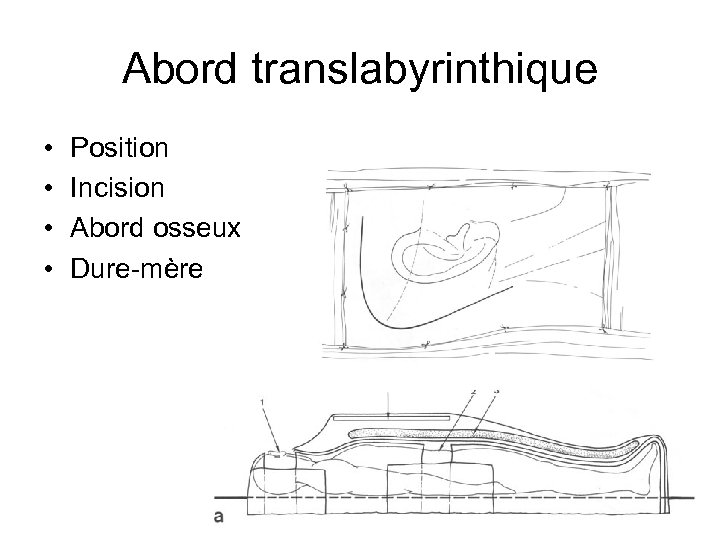

Abord translabyrinthique • • Position Incision Abord osseux Dure-mère

Abord translabyrinthique • • Position Incision Abord osseux Dure-mère